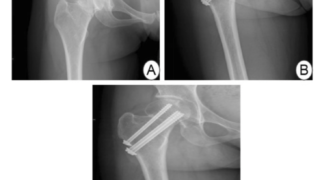

午前の病院での仕事と大腿骨頚部骨折後の骨頭壊死今朝も暖かく, 病院の敷地内の桜は満開になっていました.8時から朝の病棟回診を行い, 先週末の救急当番で搬送され入院した骨折患者さんの経過を確認しました. お元気そうで, 朝食も摂られており, ...